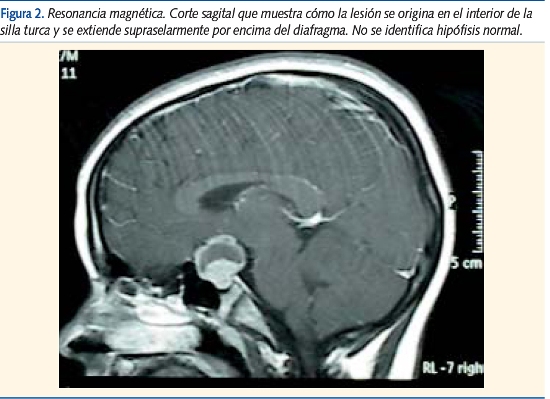

La resonancia magnética (RM) definió la porción quística supraselar de contenido proteináceo (ligeramente hiperintensa en T1 e hipointensa en T2) y la porción sólida intraselar isointensa a la sustancia gris en ambas secuencias y que realzaba intensamente tras gadolinio (figuras 2 y 3).